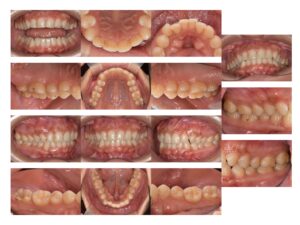

当院での妊婦検診は通常の検査項目に加え、口腔内写真を撮影し視覚的にどこか悪い箇所があるのかを見ていただくようにしております。

写真を見ながら現在の状態を確認していただき治療が必要な場合は治療に進んでいただくようにしております。